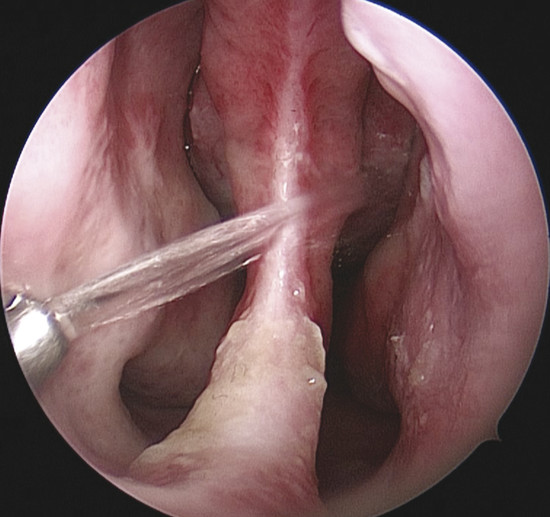

The nasal cavity receives its arterial supply from multiple branches that originated from both the internal and external carotid arteries. Of importance are the branches from the sphenopalatine, along with the superior labial artery, anterior ethmoidal artery (AEA), and greater palatine artery that nourish the Kiesselbach plexus, and therefore the anterior portion of the nasal septum, where most bleeding and perforation occur. 1 , 2 , 3 , 4 , 5 , 6

A chemical or physical damage to the normal anatomy can lead to ischemic necrosis of the septal cartilage, resulting in perforation. Any healing result around the borders of the perforation over the three layers, cartilage, and the two sides of the mucoperichondrium is probably to be thin and atrophic. Therefore, if the edges of the perforation do not heal normally, it gets covered with an atrophic layer of mucosa, producing formation of crusts and a tendency toward bleeding because of the friction of abnormal airflow forces. The turbulent abnormal air forces friction, and the mechanical peeling to relieve a sensation of congestion may result in ongoing crusting, bleeding, and enlargement. 7

When the septum is perforated, the inspired airflow going uniformly over the nasal turbinates adding heat and moisture to the air is disrupted. The inspired air loses its normal airflow pattern through the nasal cavity and begins to recirculate, producing excessive drying of the nasal mucosa that leads to its symptoms.